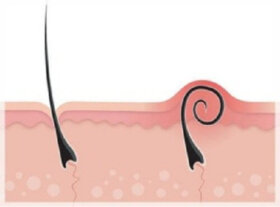

인그로운 헤어는 매우 쉽게 생길 수 있다. 털을 제거하고 싶다면 올바른 방법을 시도해야 한다. 오늘은 인그로운 헤어를 제거하는 방법을 소개한다.